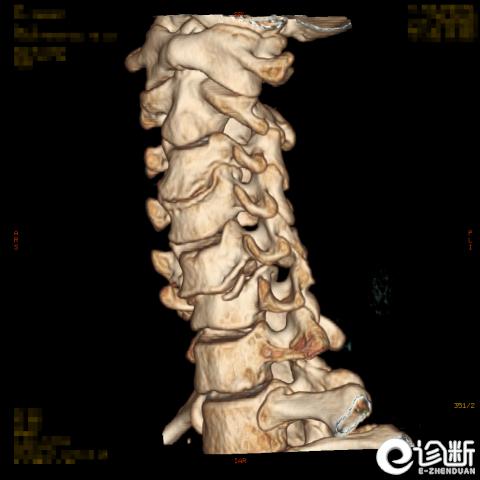

颈椎骨折

CT:显示椎管(骨折碎片可压迫椎管)

分型:

根据骨折的水平及位置:C1-Jeferson骨折:前后弓骨折

C1-侧块骨折

C2-Hangman骨折(峡部):Levine分型

C2齿突骨折1型、2型、3型

C3-7骨折: